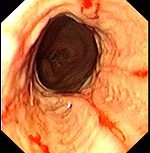

(单选题)胃镜检查如下图,诊断为()。

A:食管癌

B:反流性食管炎

C:心绞痛

D:消化性溃疡

E:贲门癌